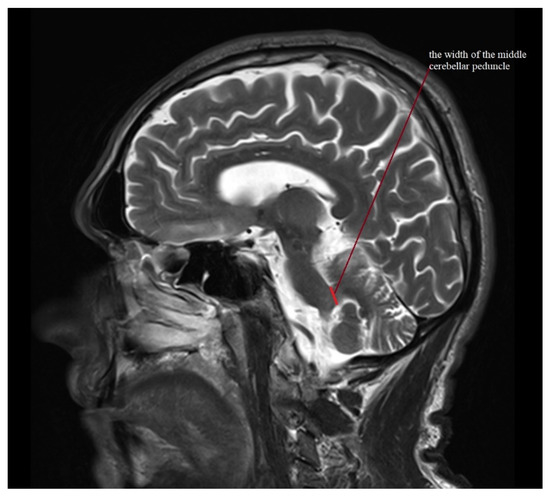

- Quattrone, A.; Nicoletti, G.; Messina, D.; Fera, F.; Condino, F.; Pugliese, P.; Lanza, P.; Barone, P.; Morgante, L.; Zappia, M.; et al. MR imaging index for differentiation of progressive supranuclear palsy from Parkinson disease and the Parkinson variant of multiple system atrophy. Radiology 2008, 246, 214–221. [Google Scholar] [CrossRef] [PubMed]

- Quattrone, A.; Morelli, M.; Nigro, S.; Quattrone, A.; Vescio, B.; Arabia, G.; Nicoletti, G.; Nisticò, R.; Salsone, M.; Novellino, F.; et al. A new MR imaging index for differentiation of progressive supranuclear palsy-parkinsonism from Parkinson’s disease. Park. Relat. Disord. 2018, 54, 3–8. [Google Scholar] [CrossRef] [PubMed]

| MRPI | 11.247 (7.758–15.429) | 1.882 ± 1.39–2.912 | 17.384 (12.025–26.626) | 4.439 ± 3.183–7.327 | 19.366 (9.343–31.303) | 6.944 ± 5.247–10.27 | 10.766 (7.163–17.151) | 2.503 ± 1.915–3.614 | 15.363 (6.582–29.025) | 5.03 ± 3.801–7.439 |

| MRPI 2.0 | 2.342 (1.252–3.463) | 0.619 ± 0.457–0.958 | 4.338 (2.526–6.306) | 1.344 ± 0.964–2.219 | 5.646 (2.595–9.838) | 2.324 ± 1.756–3.436 | 2.558 (1.41–4.549) | 0.91 ± 0.696–1.314 | 4.195 (1.953–9.285) | 1.686 ± 1.274–2.493 |